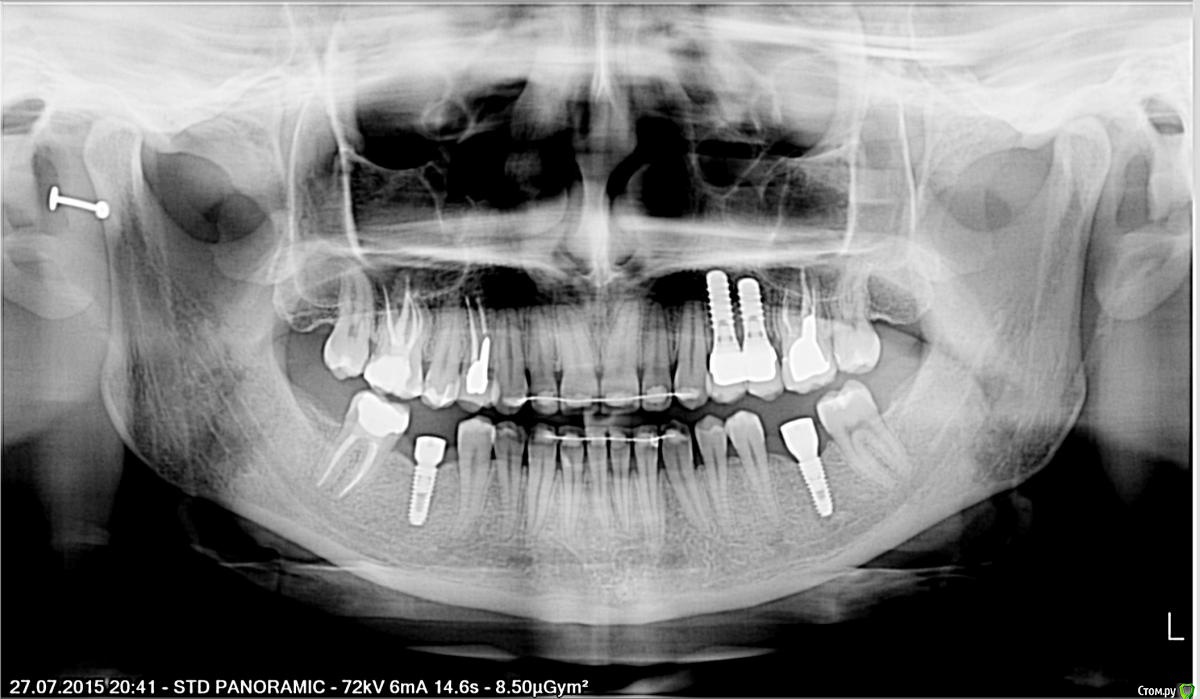

Тая.А Опубликовано 28 июля, 2015 Автор Поделиться Опубликовано 28 июля, 2015 товарищи доктора, посмотрите пож-ста снимок.Что все-таки можно сделать по поводу пластики десны,сосочка и пр. Ссылка на комментарий

andr99 Опубликовано 28 июля, 2015 Поделиться Опубликовано 28 июля, 2015 Тут еще и штрауманн с полированной шейкой.. шансы на сосочек не велики, даже с пластикой. Имплантаты действительно стоят достаточно близко. Ссылка на комментарий

Bier Опубликовано 28 июля, 2015 Поделиться Опубликовано 28 июля, 2015 А почему разные имплантаты вверху и внизу? Для создания десневого сосочка я бы предложил удалить дистальный имплантат 1 Ссылка на комментарий